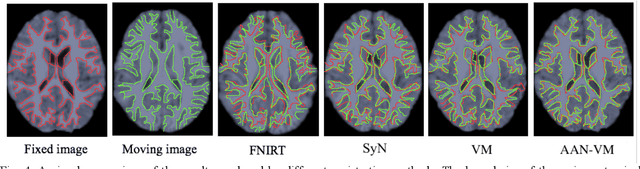

Abstract:Deformable image registration is fundamental for many medical image analyses. A key obstacle for accurate image registration is the variations in image appearance. Recently, deep learning-based registration methods (DLRs), using deep neural networks, have computational efficiency that is several orders of magnitude greater than traditional optimization-based registration methods (ORs). A major drawback, however, of DLRs is a disregard for the target-pair-specific optimization that is inherent in ORs and instead they rely on a globally optimized network that is trained with a set of training samples to achieve faster registration. Thus, DLRs inherently have degraded ability to adapt to appearance variations and perform poorly, compared to ORs, when image pairs (fixed/moving images) have large differences in appearance. Hence, we propose an Appearance Adjustment Network (AAN) where we leverage anatomy edges, through an anatomy-constrained loss function, to generate an anatomy-preserving appearance transformation. We designed the AAN so that it can be readily inserted into a wide range of DLRs, to reduce the appearance differences between the fixed and moving images. Our AAN and DLR's network can be trained cooperatively in an unsupervised and end-to-end manner. We evaluated our AAN with two widely used DLRs - Voxelmorph (VM) and FAst IMage registration (FAIM) - on three public 3D brain magnetic resonance (MR) image datasets - IBSR18, Mindboggle101, and LPBA40. The results show that DLRs, using the AAN, improved performance and achieved higher results than state-of-the-art ORs.